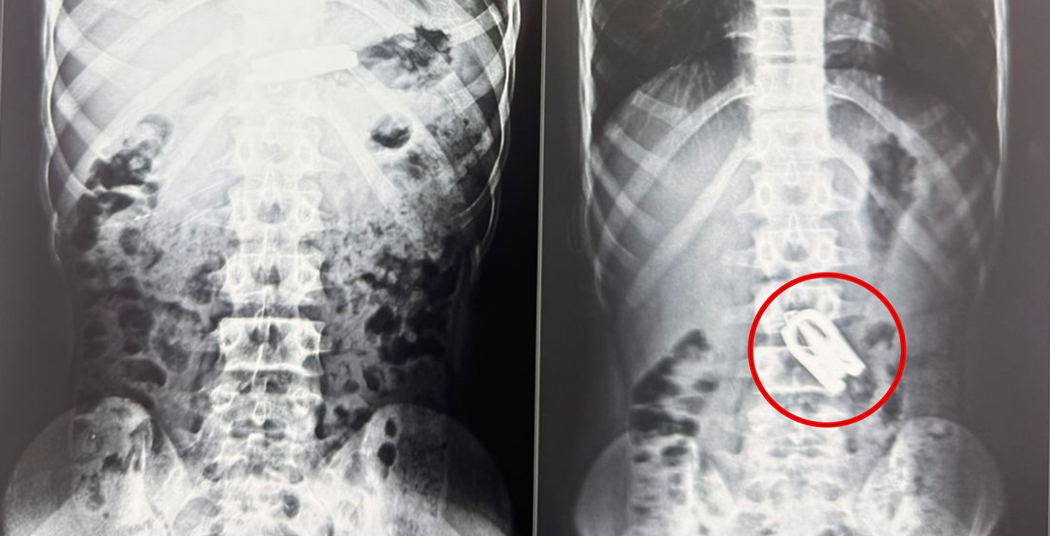

एक्स-रे र सिटी स्क्यानको आधारमा उनको पेटको ठुलो आन्द्राभित्र कैँची अड्किएको पुष्टि भयो । घटना अत्यन्तै जटिल र संवेदनशील रहेपनि नोबेलमा सफल शल्यक्रिया भएको हो ।

उपचारमा संलग्न डाक्टर भट्टराईका अनुसार बालकको आन्द्रामा अड्किएको कैँचीले थप जटिलता ल्याउन सक्थ्यो । तर समयमै ल्याप्रोस्कोपी सर्जरीमार्फत कैँची निकाल्न सफल हुँदा बिरामीको अवस्था स्थिर रहेको उनको भनाइ छ ।